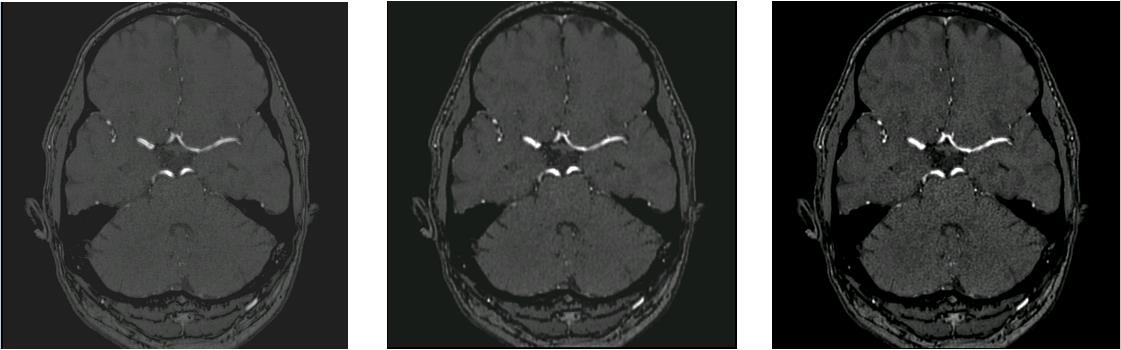

Time-of-Flight Magnetic Resonance Angiographs (TOF-MRAs) enable visualization and analysis of cerebral arteries. This analysis may indicate normal variation of the configuration of the cerebrovascular system or vessel abnormalities, such as aneurysms. A model would be useful to represent normal cerebrovascular structure and variabilities in a healthy population and to differentiate from abnormalities. Current anomaly detection using autoencoding convolutional neural networks usually use a voxelwise mean-error for optimization. We propose optimizing a variational-autoencoder (VAE) with structural similarity loss (SSIM) for TOF-MRA reconstruction. A patch-trained 2D fully-convolutional VAE was optimized for TOF-MRA reconstruction by comparing vessel segmentations of original and reconstructed MRAs. The method was trained and tested on two datasets: the IXI dataset, and a subset from the ADAM challenge. Both trained networks were tested on a dataset including subjects with aneurysms. We compared VAE optimization with L2-loss and SSIM-loss. Performance was evaluated between original and reconstructed MRAs using mean square error, mean-SSIM, peak-signal-to-noise-ratio and dice similarity index (DSI) of segmented vessels. The L2-optimized VAE outperforms SSIM, with improved reconstruction metrics and DSIs for both datasets. Optimization using SSIM performed best for visual image quality, but with discrepancy in quantitative reconstruction and vascular segmentation. The larger, more diverse IXI dataset had overall better performance. Reconstruction metrics, including SSIM, were lower for MRAs including aneurysms. A SSIM-optimized VAE improved the visual perceptive image quality of TOF-MRA reconstructions. A L2-optimized VAE performed best for TOF-MRA reconstruction, where the vascular segmentation is important. SSIM is a potential metric for anomaly detection of MRAs.